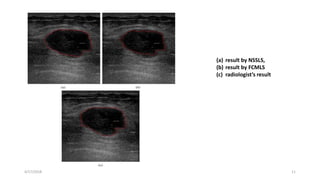

(a) result by NSSLS,

(b) result by FCMLS

(c) radiologist’s result